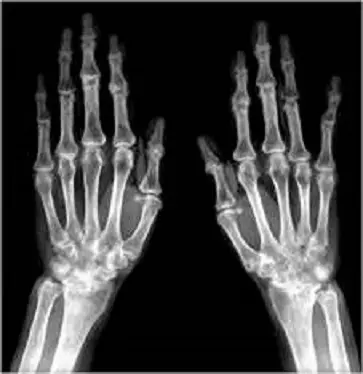

57歲女性雙手多處關節腫痛,雙手X光檢查如附圖,最可能的診斷為何?

X光片為雙手掌側正位(PA view):

- 關節空隙:可見第二至第四掌指(MCP)關節及近端指間(PIP)關節均勻且對稱地狹窄,遠端指間(DIP)關節則相對保存。

- 骨質改變:各關節周圍明顯骨質疏鬆(periarticular osteopenia),未見骨質增生或明顯骨硬化。

- 骨侵蝕:多處關節緣出現銳利、非增生性(non-proliferative)的邊緣侵蝕(marginal erosions),尤其在MCP關節頭可見不規則侵蝕缺損。

- 關節排列:數根手指於MCP關節處向尺側偏移(ulnar deviation)並有輕度關節亞脫位現象。

- 軟組織:輕度軟組織腫脹,但無明顯鈣化或大塊tophi。

這些表現符合慢性、對稱、炎性關節病變,主要累及MCP/PIP,並伴隨周圍骨質疏鬆及Marginal erosions,提示類風濕性關節炎。